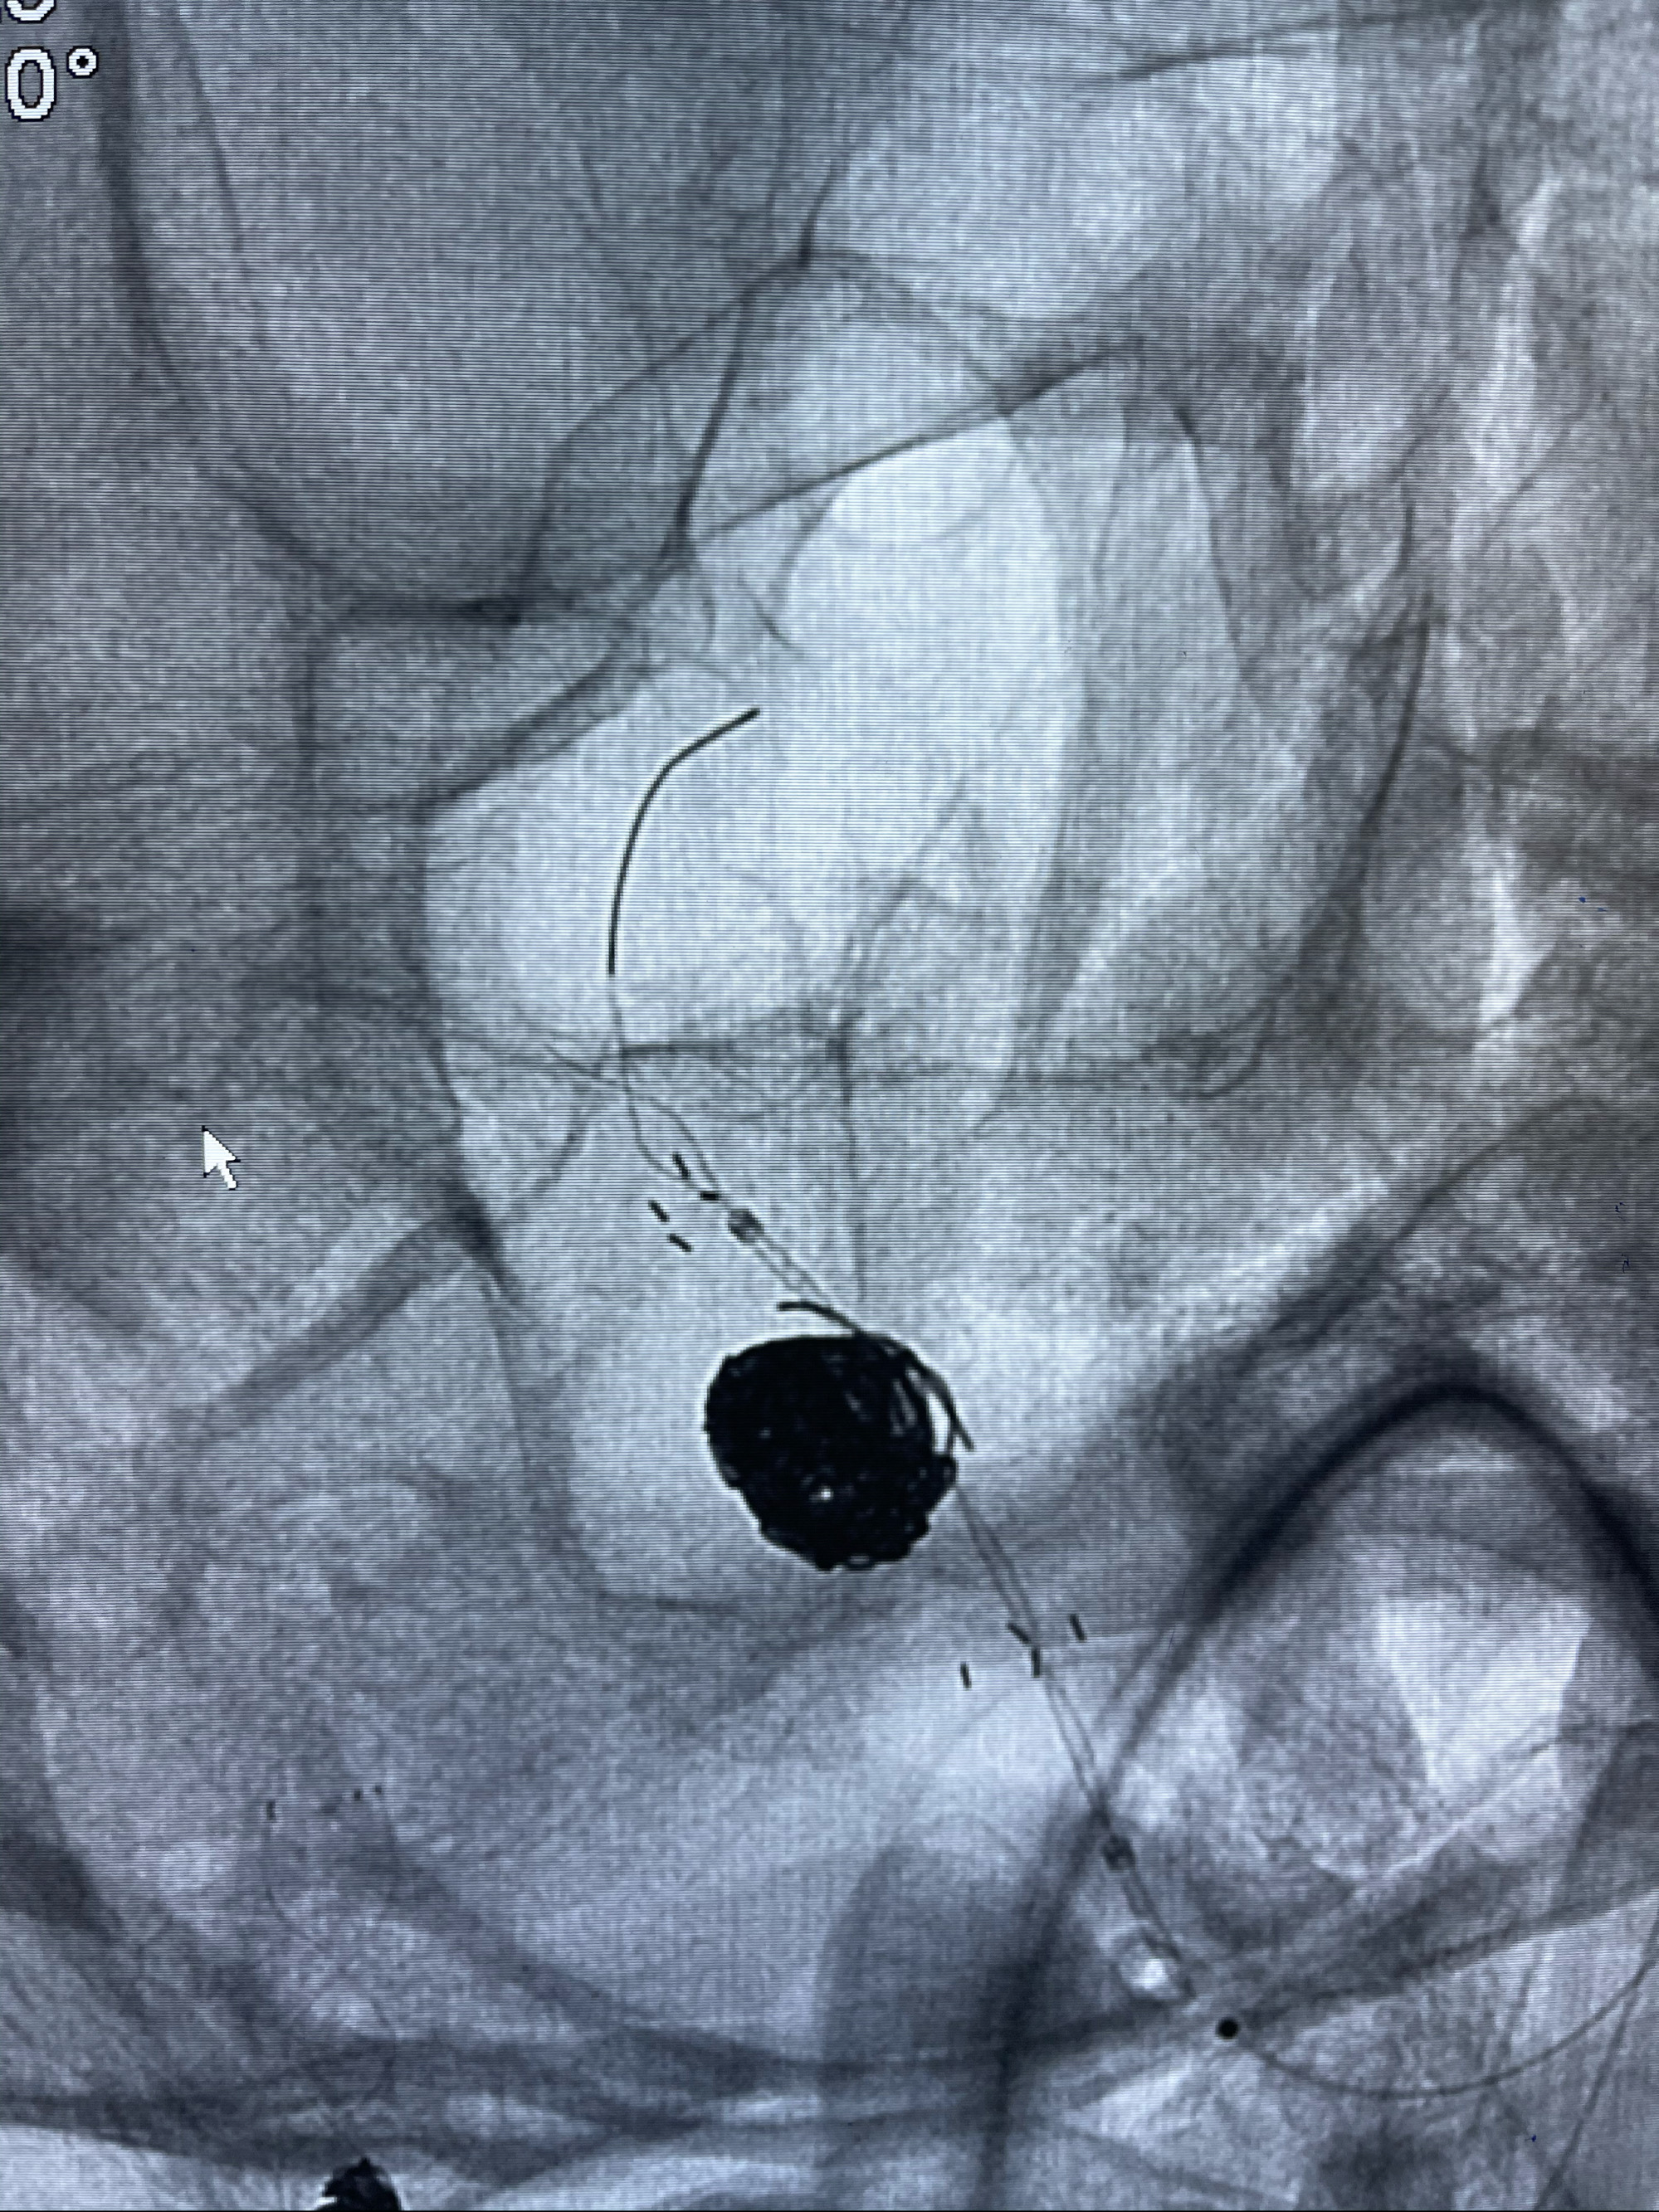

即刻造影

支架到位

支架释放,透视下

术后即刻CT